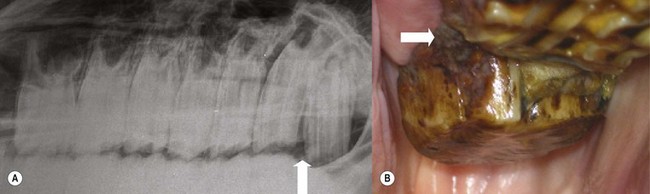

Fig. 8.19

(A) The occlusal surface of a 307 with multiple, branched subdivisions of pulp chambers 1 and 2 caused by dysplastic enamel. The dysplastic enamel has altered the overall shape of the tooth, causing it to poorly fit its alveolus, resulting in some localized periodontal food pocketing and periodontitis (site indicated by superimposed red lines).

(From Dacre et al,26 with permission from The Veterinary Journal.)

image

(B) The mid-tooth section shows all pulp chambers to be empty. The enamel dysplasia has caused reduced dentinal thickness, and the peripheral cementum has become very infolded, appearing like maxillary infundibula, i.e., completely surrounded by enamel. A new cheek teeth pulp horn numbering system is now in use (see Chapter 5).